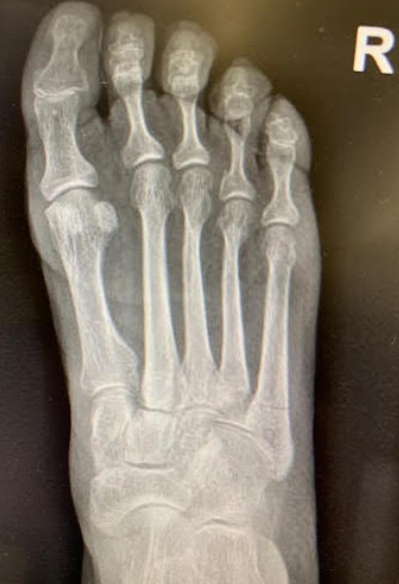

Does Your Toe Hurt That Much?

A 22 year old football player limps to the sideline after catching a sideline pass requiring him to land on his toes to complete the catch in bounds. Now he is complaining of pain at his right 1st MTP saying that he thinks his “toe popped out”.